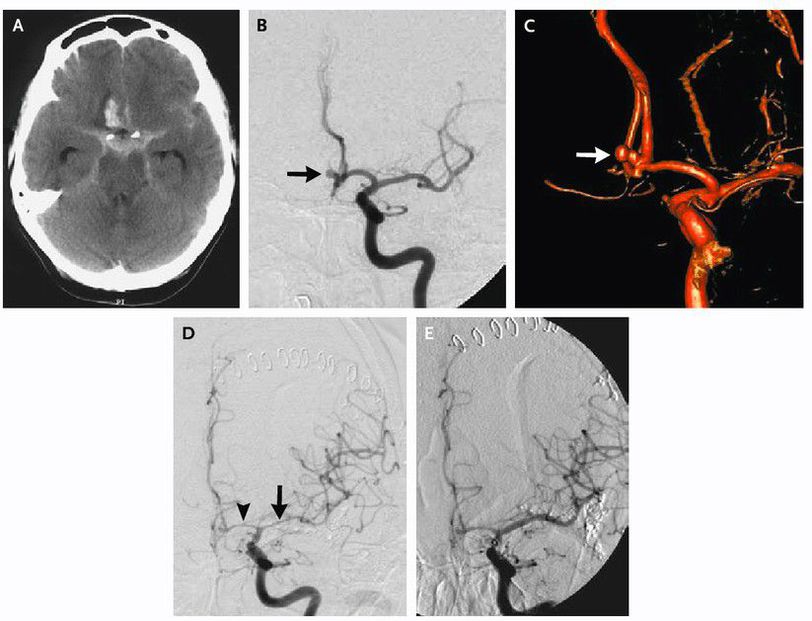

Subarachnoid Hemorrhage in a 69-Year-Old Woman. This patient, who had a long-standing history of smoking and hypertension, presented to the emergency room with severe headache with nausea and vomiting for four hours and had meningismus on physical examination. Initial computed tomography (CT) of the head revealed a subarachnoid hemorrhage, a right frontal hematoma suggestive of an anterior communicating artery aneurysm, and hydrocephalus (Panel A). An external ventricular drain was inserted on arrival. Digital-subtraction cerebral angiography (oblique view) showed an aneurysm stemming from the anterior communicating artery (Panel B, arrow). Three-dimensional digital-subtraction angiography clearly showed the bilobed, irregular nature of the aneurysm (Panel C, arrow). The patient underwent craniotomy and sur- gical clipping of the aneurysm, with good postoperative recovery. Six days after admission, the patient had rapid onset of global aphasia and right hemiparesis. Transcranial Doppler ultrasonography demonstrated a severe eleva- tion in blood-flow velocities (>200 cm per second) in the left middle and anterior cerebral arteries. Angiography showed considerable vasospasm (Panel D) in the proximal segments of the left anterior arteries (arrowhead) and middle cerebral arteries (arrow). The patient underwent transluminal balloon angioplasty of the left middle cerebral artery, and direct vasodilators (papaverine and verapamil) were infused into the left anterior cerebral artery with good resolution of the vasospasm (Panel E). The patient’s clinical course evolved favorably, and she was indepen- dent three months after presentation